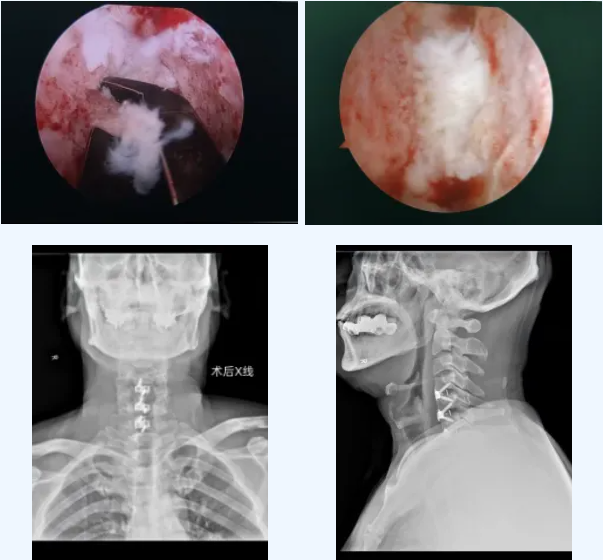

面对徐先生明确的脊髓压迫和神经损伤,必须尽快手术减压。李永革主任团队经周密评估,为患者量身定制了方案:采用 UBE(单侧双通道内镜)技术施行颈前路微创减压融合术。

视野放大20倍:4K高清内镜让压迫部位一目了然,实现“可视化”精准操作;

减压更彻底、更安全:可在镜下轻柔、彻底地切除脱出的椎间盘,解除脊髓压迫,极大避免损伤周边神经血管;

保留结构:无需大范围切除椎体,保留了颈椎原有稳定结构;

康复更快:配合使用低剖面内固定,减少术后吞咽不适,特别有利于中老年患者快速恢复。

手术由李主任主刀,顺利清除了致压物,脊髓压迫彻底解除,颈椎稳定性也得到重建。整个过程出血少、创伤小。